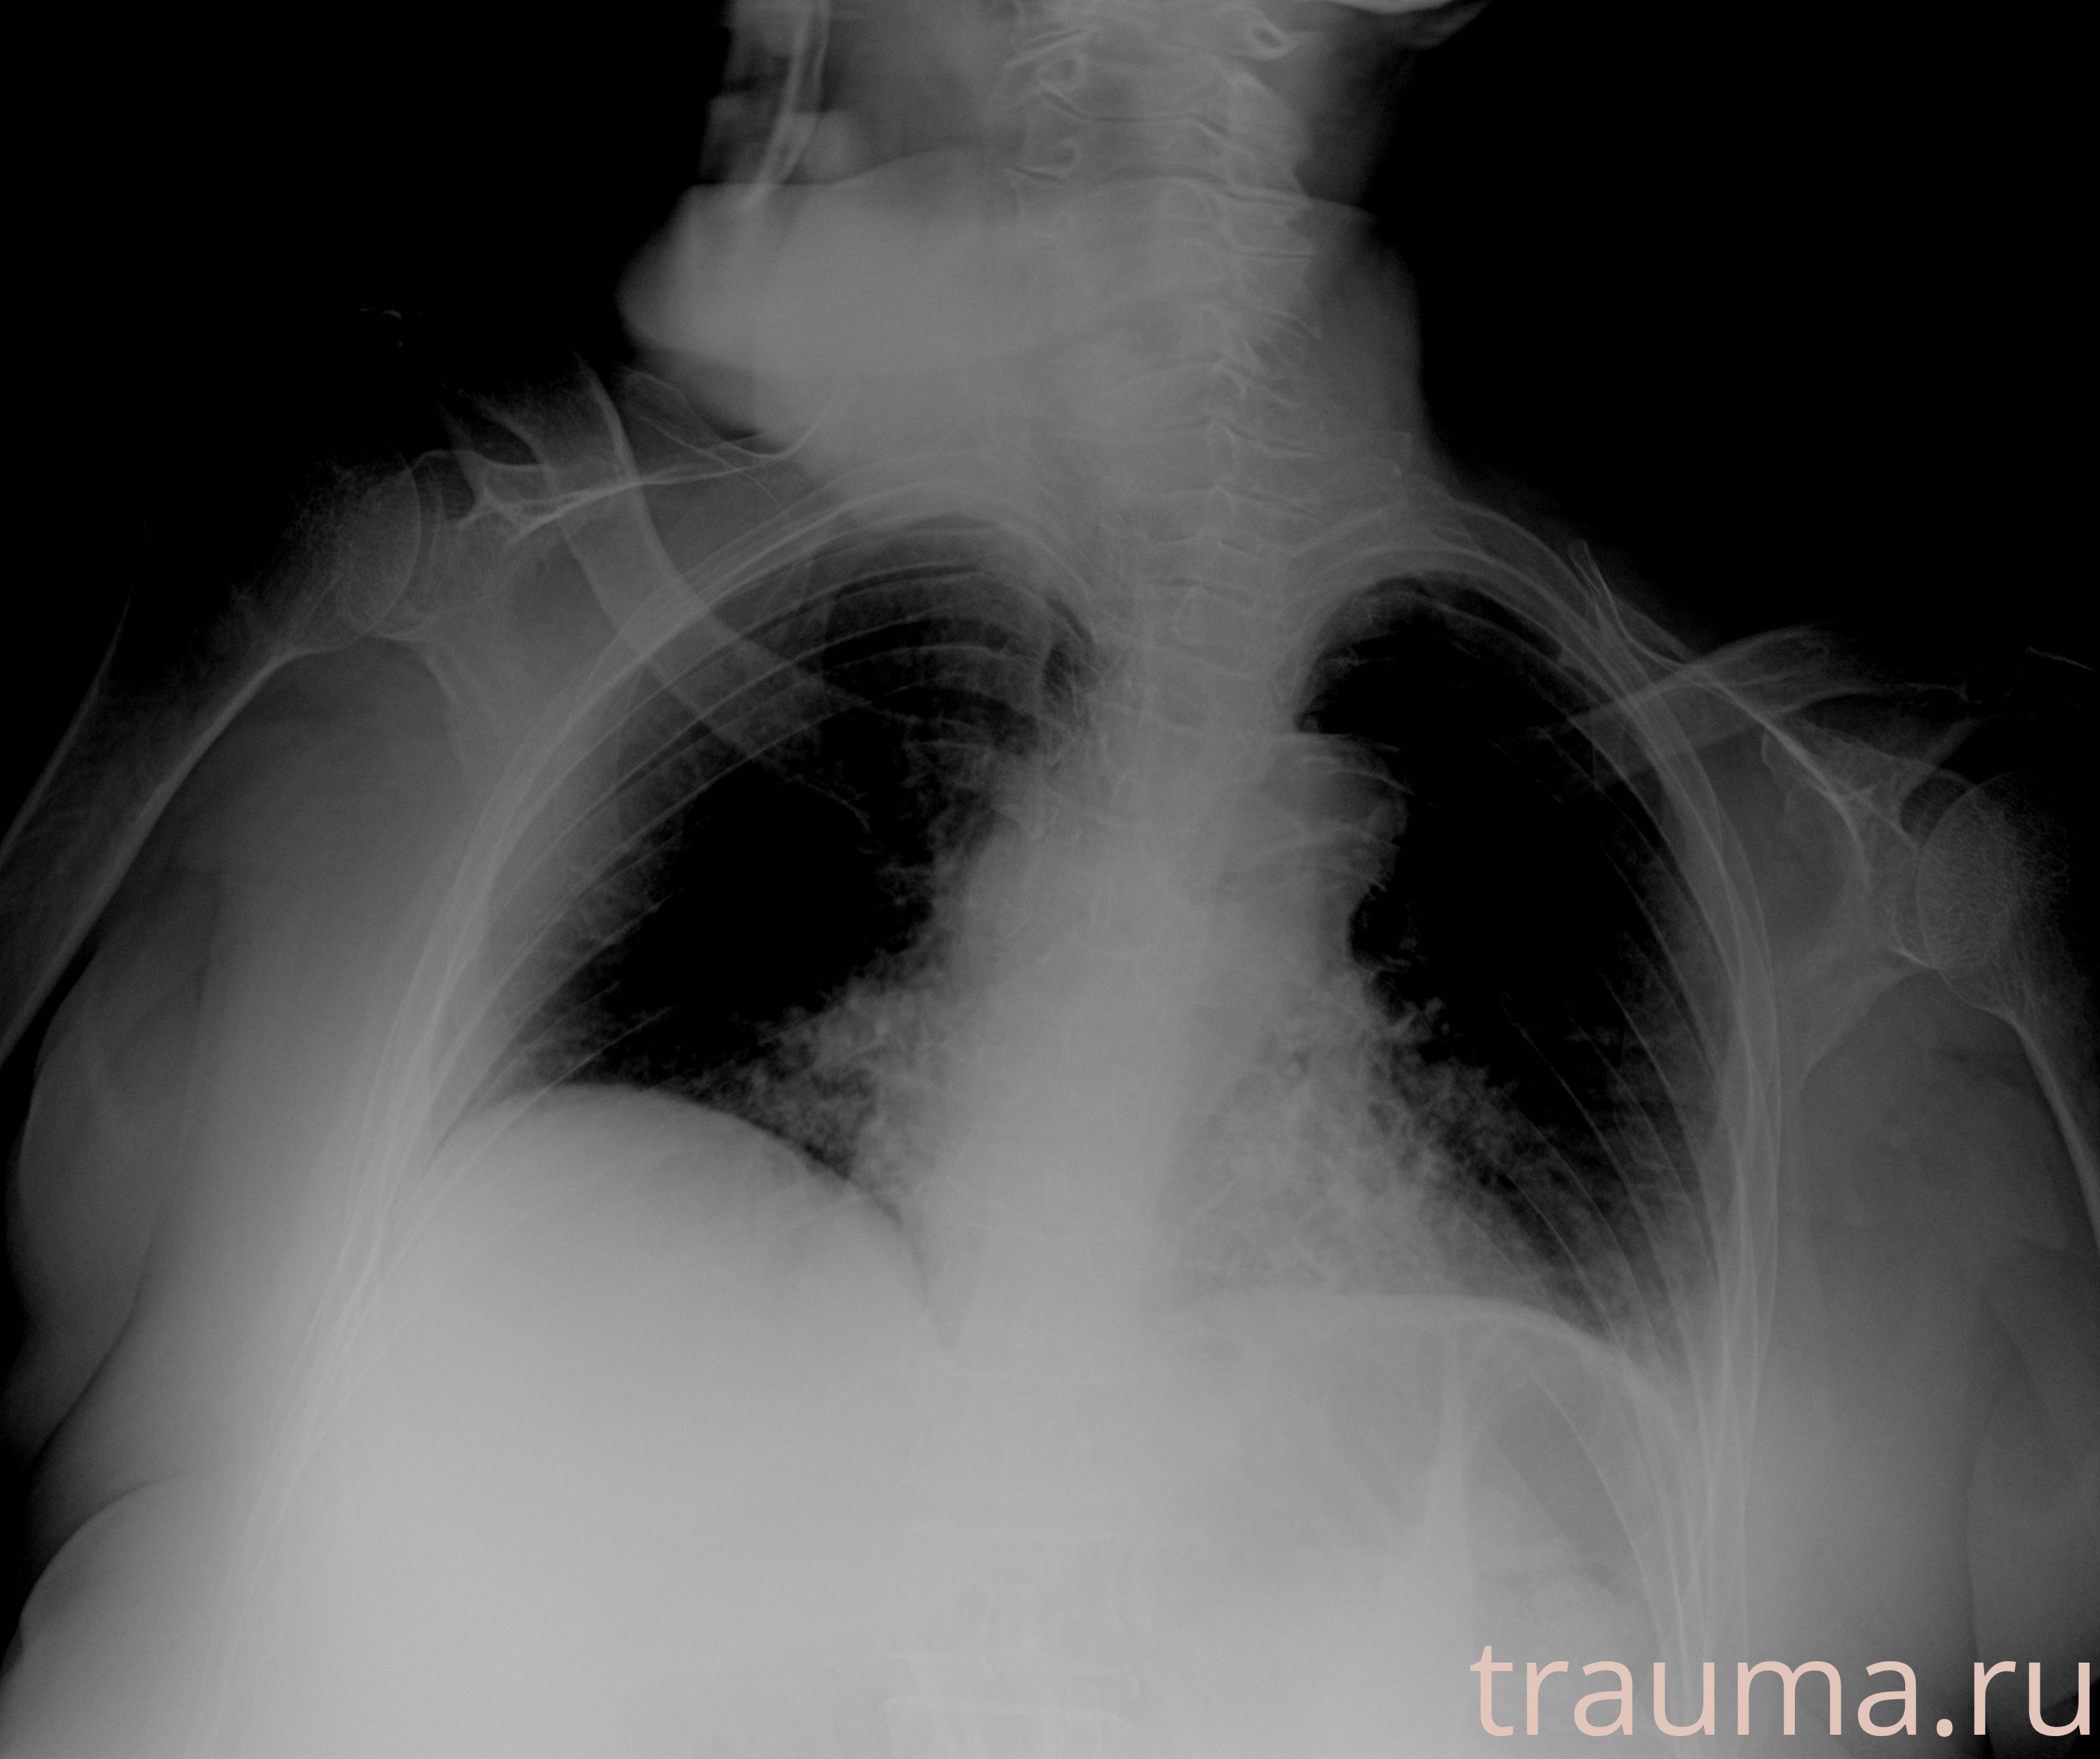

Рентген на дому: по вашему адресу приезжает врач-рентгенолог, травматолог-ортопед с мобильным рентгеновским аппаратом, проводит диагностику травмы или заболевания, делает необходимые рентгенограммы, дает рекомендации по дальнейшему лечению. Получить качественные снимки в домашних условиях возможно благодаря уникальной методике, разработанной МосРентген Центром для института  Склифосовского

при переломе шейки бедра и пневмонии от компании МосРентген Центр - партнера Института имени Склифосовского